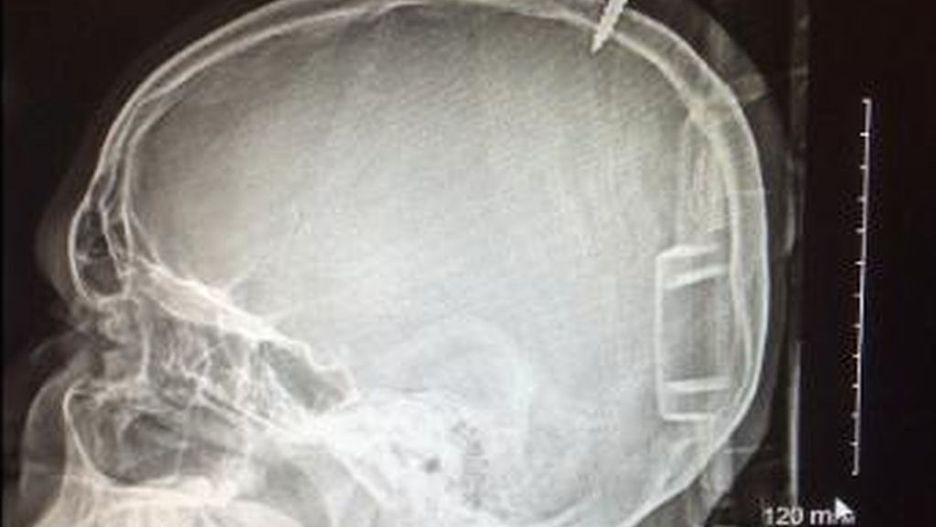

Rentgen głowy chłopca z Maryland.

Źródło zdjęć: © Twitter | cnn

Darius Foreman spędził sobotnie popołudnie na budowie domku na drzewie. W pewnym momencie omsknęła mu się noga. 13-latek spadł na ziemię, a razem z nim 2-metrowa deska naszpikowana metalowymi wkrętami. Belka trafiła chłopca w głowę w taki sposób, że jedna z wystających śrub wbiła mu się w sam środek czaszki. Przeżył wypadek tylko dlatego, że wkręt przebił akurat to miejsce, które oddziela obie półkule mózgowe.

13-letni Darius Foreman spędził 7 godzin z deską wbitą w czaszkę. Sama operacja wyjmowania śruby zajęła lekarzom przeszło 2 godziny. Zabieg zakończył się jednak sukcesem. Chłopiec nie ma uszkodzonego mózgu. W zeszły czwartek obchodził 13. urodziny. Z tej okazji lekarze wypisali go ze szpitala.